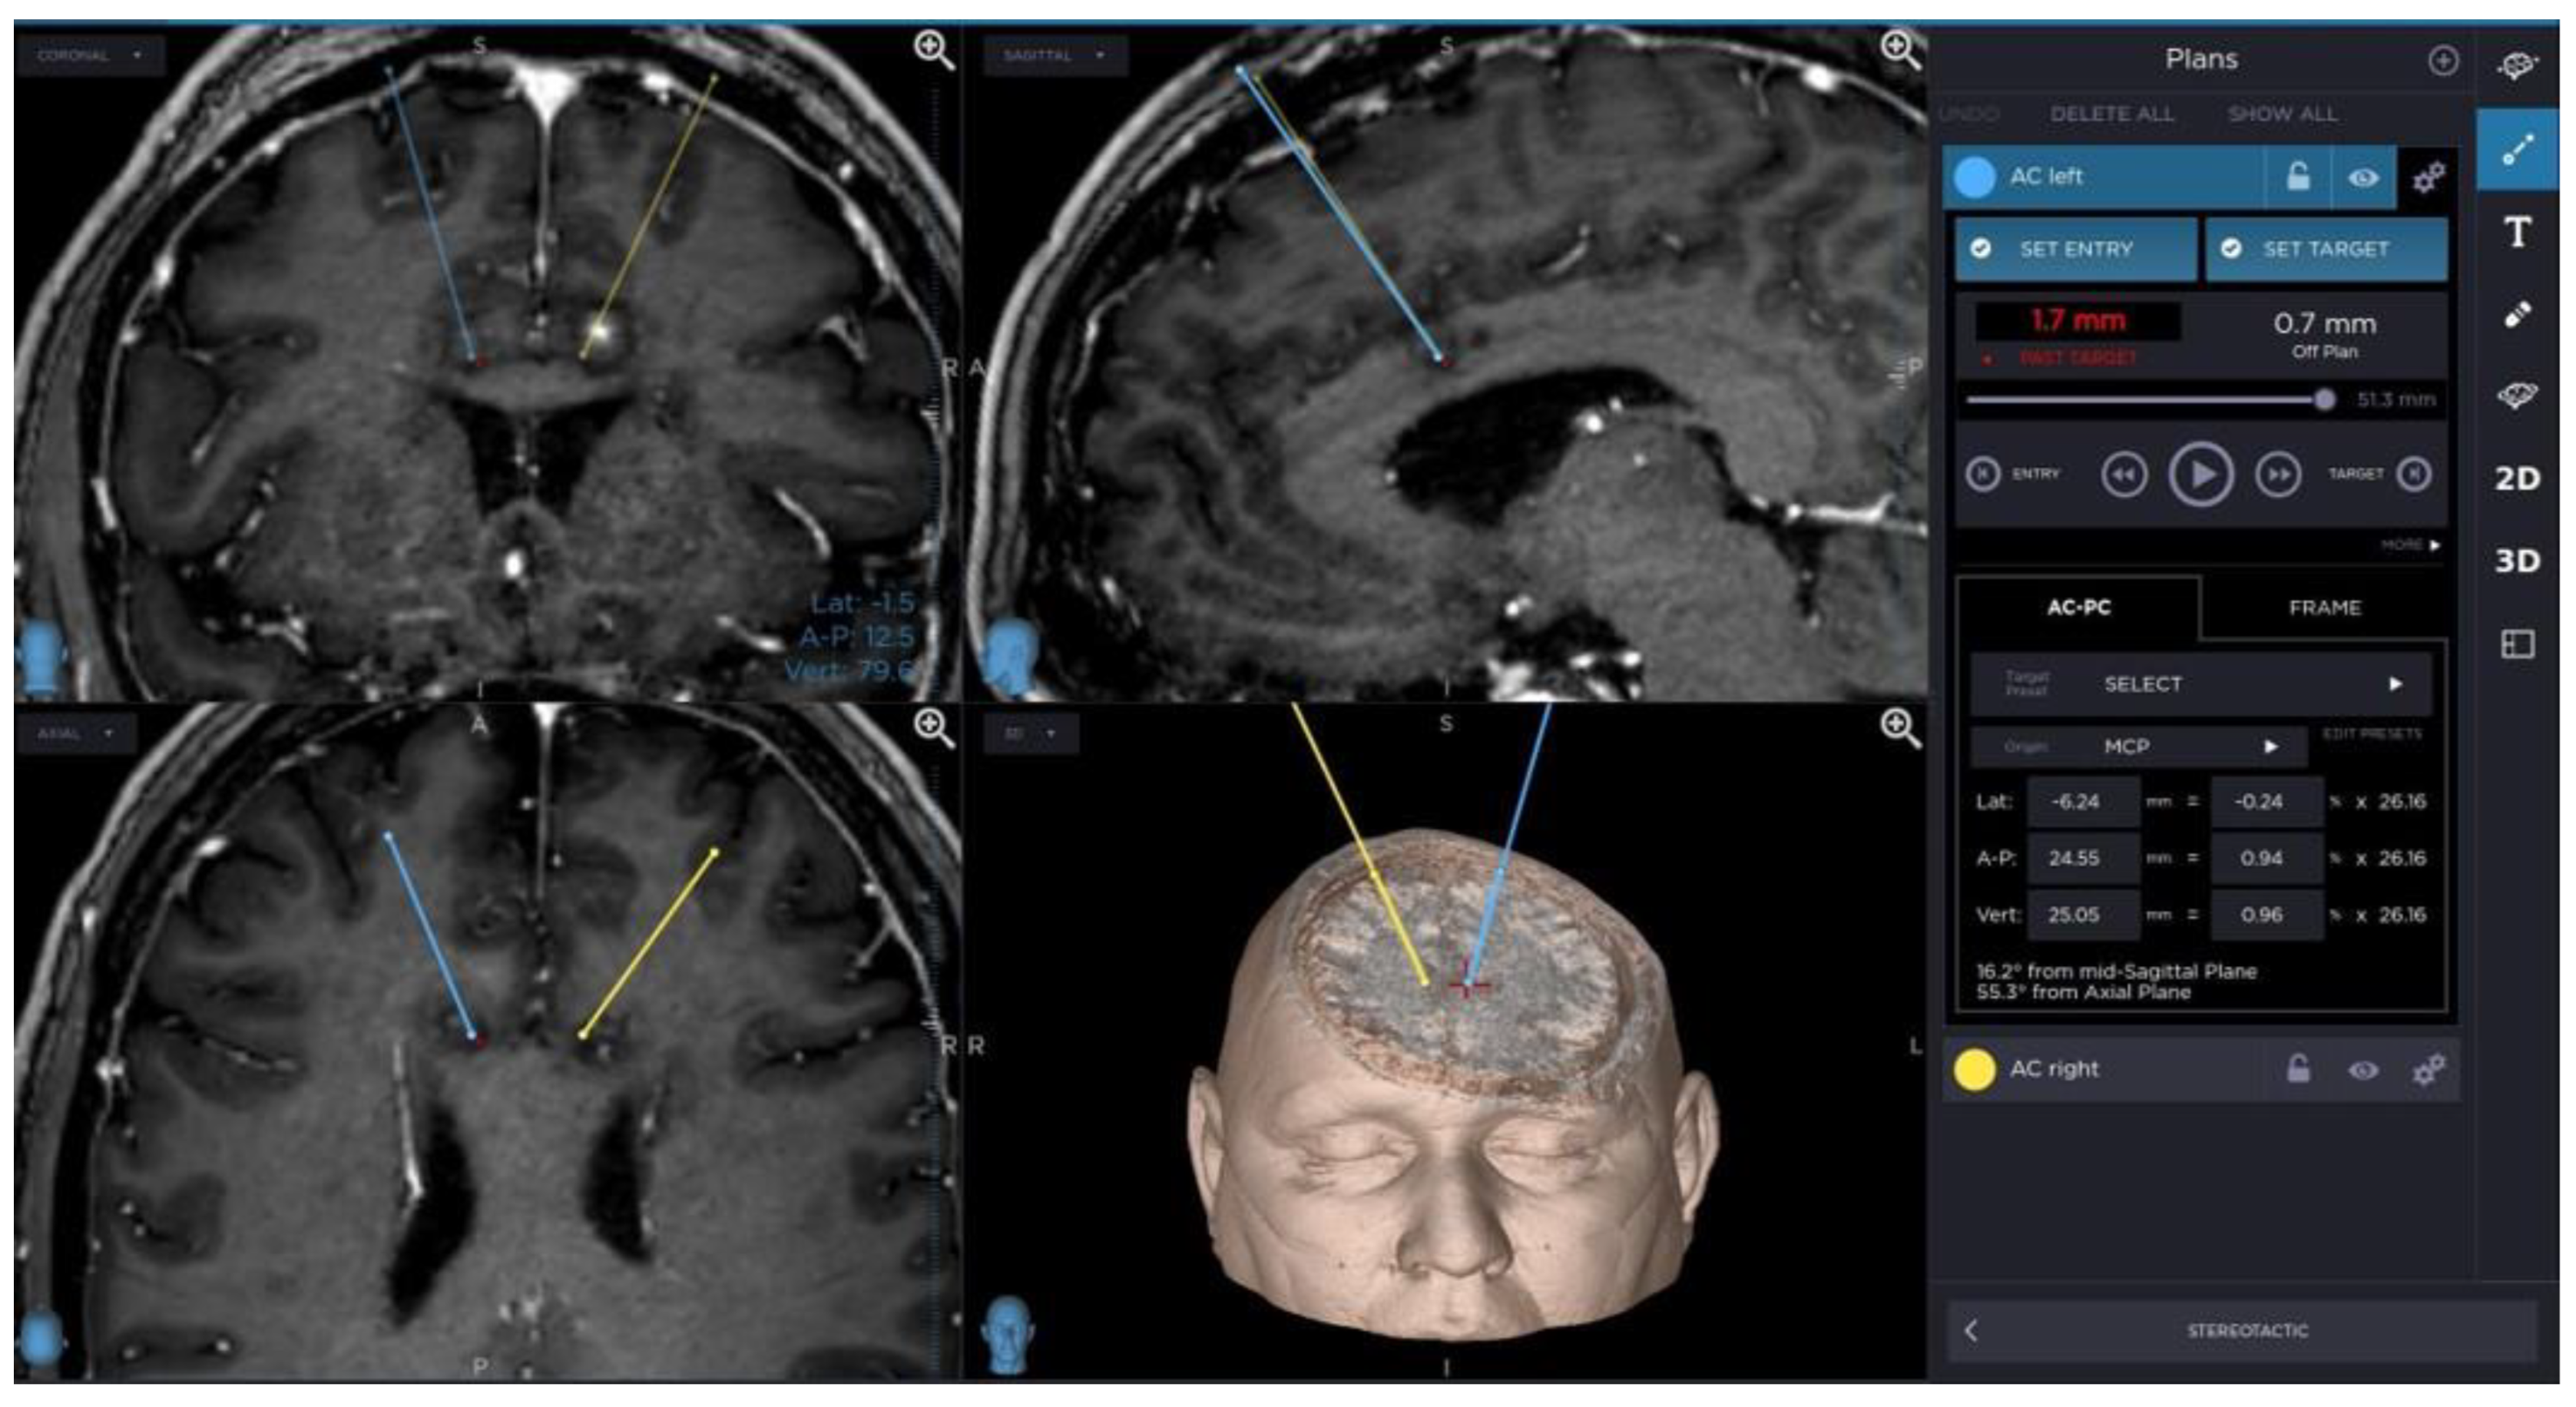

Changes in the anatomy of forceps minor before and after cingulotomy are presented in Figure 2 and Figure 3; moreover, arcuate fasciculus before and after cingulotomy is presented in Figure 4 and Figure 5.

Figure 2. Forceps minor before cingulotomy.